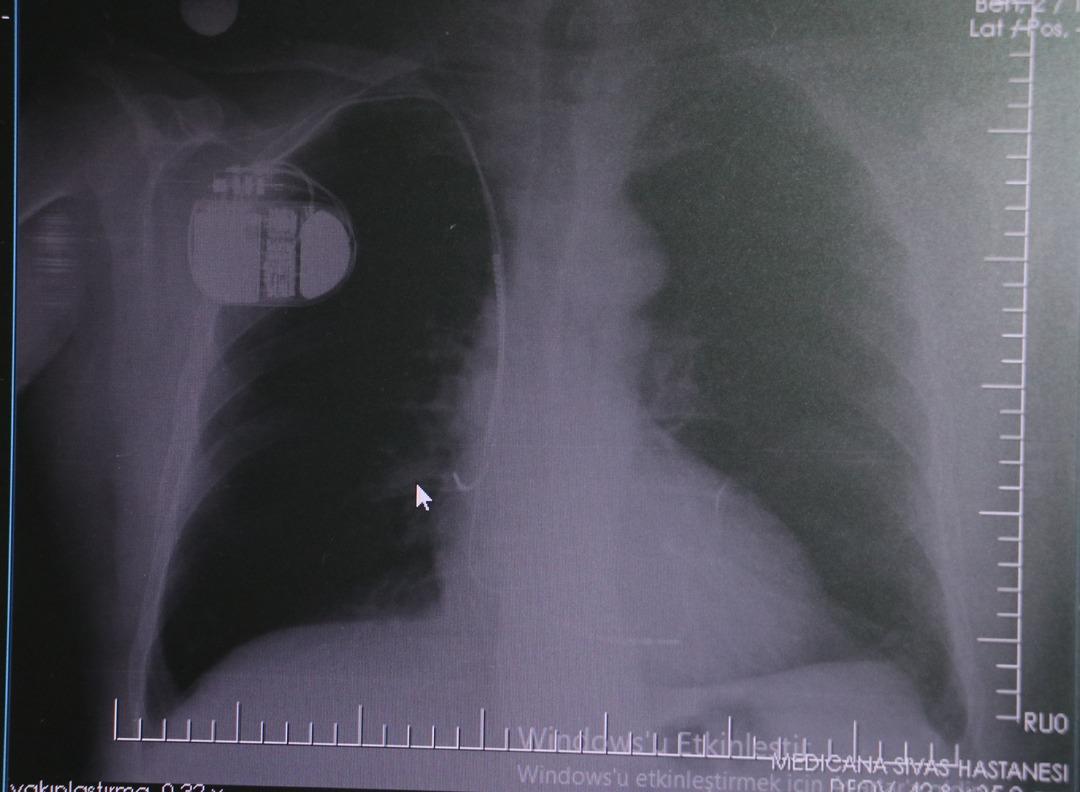

Kalp krizi sonrası kalp dokusunun zarar gördüğünü belirten İsmail Erdoğu, şöyle konuştu: “Kalp hastalığı günümüzde dünyada en sık görülen ölüm nedenlerinden biridir. Kalp hastalıklarının pek çok grubu vardır. Kalp hastalığı dediğimizde sadece kalpte stent bulunan ve damar sorunları olan kişileri kastetmiyoruz. Aynı zamanda hipertansiyon ve şeker hastalığı olan hastalar da kalp hastalığına adaydır. Toplumun yaklaşık %30-35’ini kapsıyoruz. Oldukça yaygın bir hastalıktır ve bu konuda teknolojik ve tıbbi anlamda ciddi gelişmeler yaşanmıştır. Son 30 yılda insanlar kalp rahatsızlığı nedeniyle hastaneye kaldırıldı.” “Hastaneye yattıktan sonra hayatta kalmak artık mümkün. Kalp krizinden kurtulmanın belli bir maliyeti var. Kalp krizinden sonra kalp yetmezliği ortaya çıkıyor. Kalp yetmezliği olan hastalarda aritmiler, ani ölümler gibi sorunlar ortaya çıkabiliyor. Hastaların bu uzun vadeli rahatsızlıklardan kendilerini korumak için mutlaka kalp piline ihtiyaçları var” dedi.

MR makinesine kalp pili takılmasının mümkün olduğunu belirten Erdoğu, şöyle konuştu: “Çok büyük bir ameliyat değil ama yine de ciddi bir cerrahi işlem. Kalp pili tıpta son 30 yılın en büyük gelişmesi. Aslında bilgisayarın minyatürleştirilmiş hali olup insan vücuduna yerleştirilen bir tedavi. İnsan ömrünü önemli ölçüde uzatan bir tedavi. İnsanlar şokla hayata tutunurken, pil olmasaydı öleceğini düşündüğümüz çok sayıda hastamız var. Bu özelliğimiz Kalp pili uygun hastalarda ani ölümü önler, ritmi düzeltecek sağlık uzmanı ya da defibrilatör yoksa hastayı hayatta tutmak mümkün değildir. Hastalarımız “kalp pilim var” dediğinde hastalıktan kurtulurlar. Örneğin mikser kullanmak ya da kolu sallayacak herhangi bir hareket kalp pilini olumsuz etkileyebilir. Soğuk havalarda vücutta meydana gelen şiddetli titremeler kalp pilinin hafızasını karıştırıp gereksiz şoklara neden olabilir.